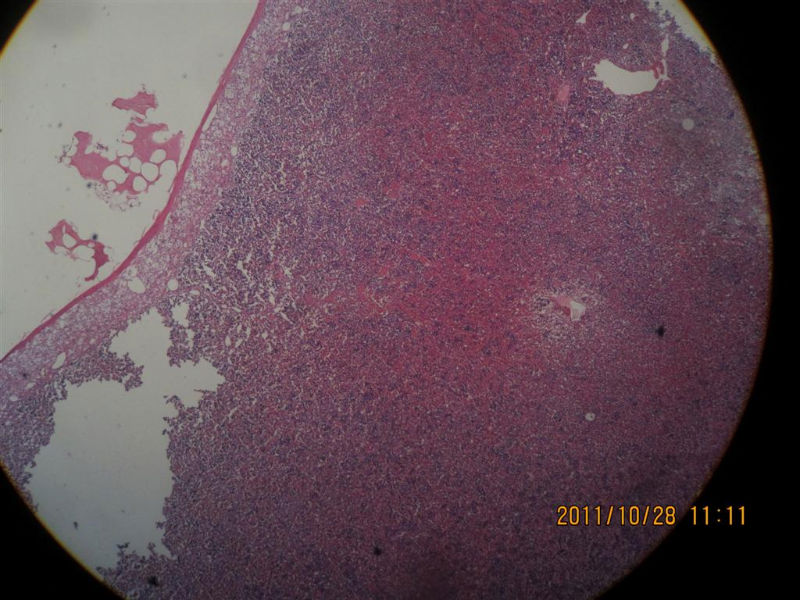

髓脂肪瘤